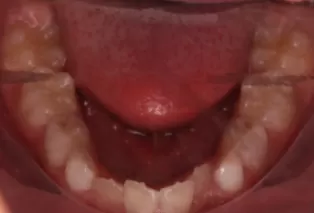

Photos intra-orales après traitement